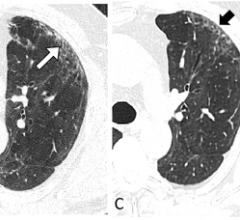

Aug. 19, 2025 — Calidar, Inc., a start-up in precision diagnostic imaging formed out of Duke University, recently ...